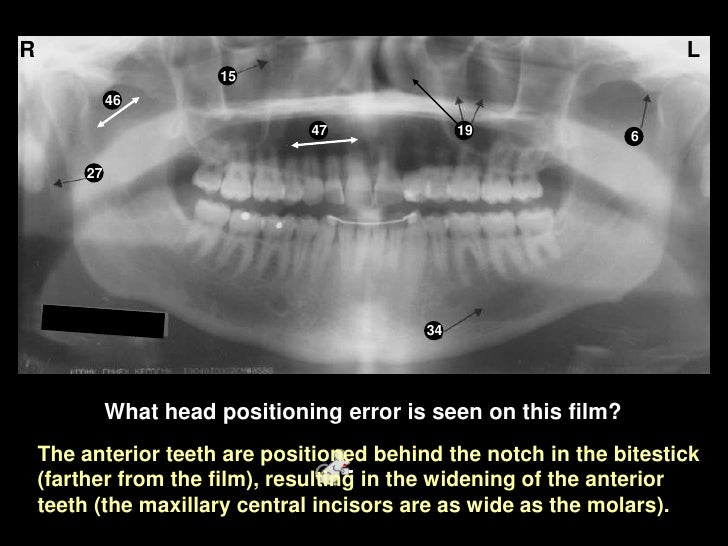

Self Study-pan-anatomy

positioning foramen

2015 radiology revision. Panoramic landmarks anatomical dental anatomy radiograph radiographs ppt lecture oral dentistry assistant hygiene note study tooth dentallecnotes pdf sinus uvula. 3 radio. anatomy.&interpert i